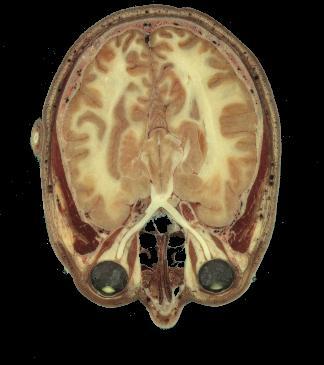

Un homme et une femme ont donné leur corps à la science et accepté d'être découpés après leur mort (l'homme était un condamné à mort américain....).

Les coupes anatomiques réalisées tous les millimètres pour l'homme, tous les 1/3 de millimètre pour la femme ont été numérisées et tout internaute peut appeler n'importe quelle coupe (axiale, coronale ou saggitale).

Bien évidemment, on n'a pas fait trois coupes (question pratique qui vient tout de suite à l'esprit des élèves !) mais une seule, axiale. Les coupes coronales et parasagittales ont été obtenues par reconstitution (d'où la présence parfois de bandes ou de décalages).

Coupes anatomiques d'un homme ou d'une femme

Vous pourrez choisir entre homme et femme et entre tête et corps entier.